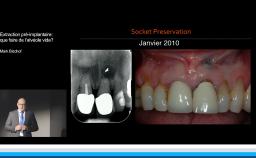

• de déterminer le bon timing de chirurgie implantaire post extractionnelle

• de réfléchir sur la préservation à moyen-long terme de l’os autour des implants

• Ridge Preservation